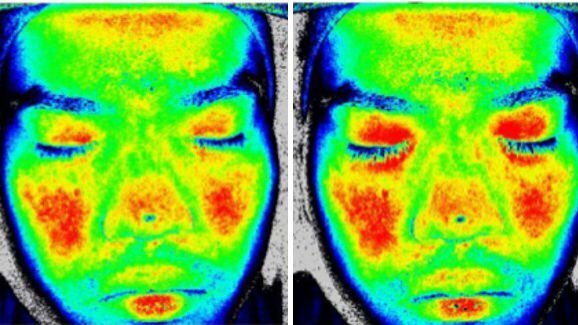

TÓQUIO, Japão: Pesquisadores japoneses identificaram novas evidências entre a palatabilidade de vários sabores e a circulação em diferentes áreas da face. Em um estudo recentemente publicado eles concluíram que que sabores percebidos como agradáveis pelos participantes do estudo aumentavam a circulação sanguínea ao redor dos olhos, enquanto sabores azedos influenciavam a circulação em outras áreas faciais.

Durante o experimento os pesquisadores coletaram informações sobre o fluxo sanguíneo na pele da testa, pálpebras, nariz e bochechas dos participantes, utilizando feixes de laser fluxográfico antes e durante a ingestão dos fluidos.

Eles perceberam que o fluxo sanguíneo nas pálpebras tinha aumento significativo em resposta ao molho de pimenta, suco de laranja e sopa, enquanto o fluxo sanguíneo na testa, nariz e bochechas diminuía em resposta ao chá amargo. “Esses resultados sugerem que a resposta da circulação facial reflete o grau de palatabilidade dos alimentos”, concluíram os pesquisadores.